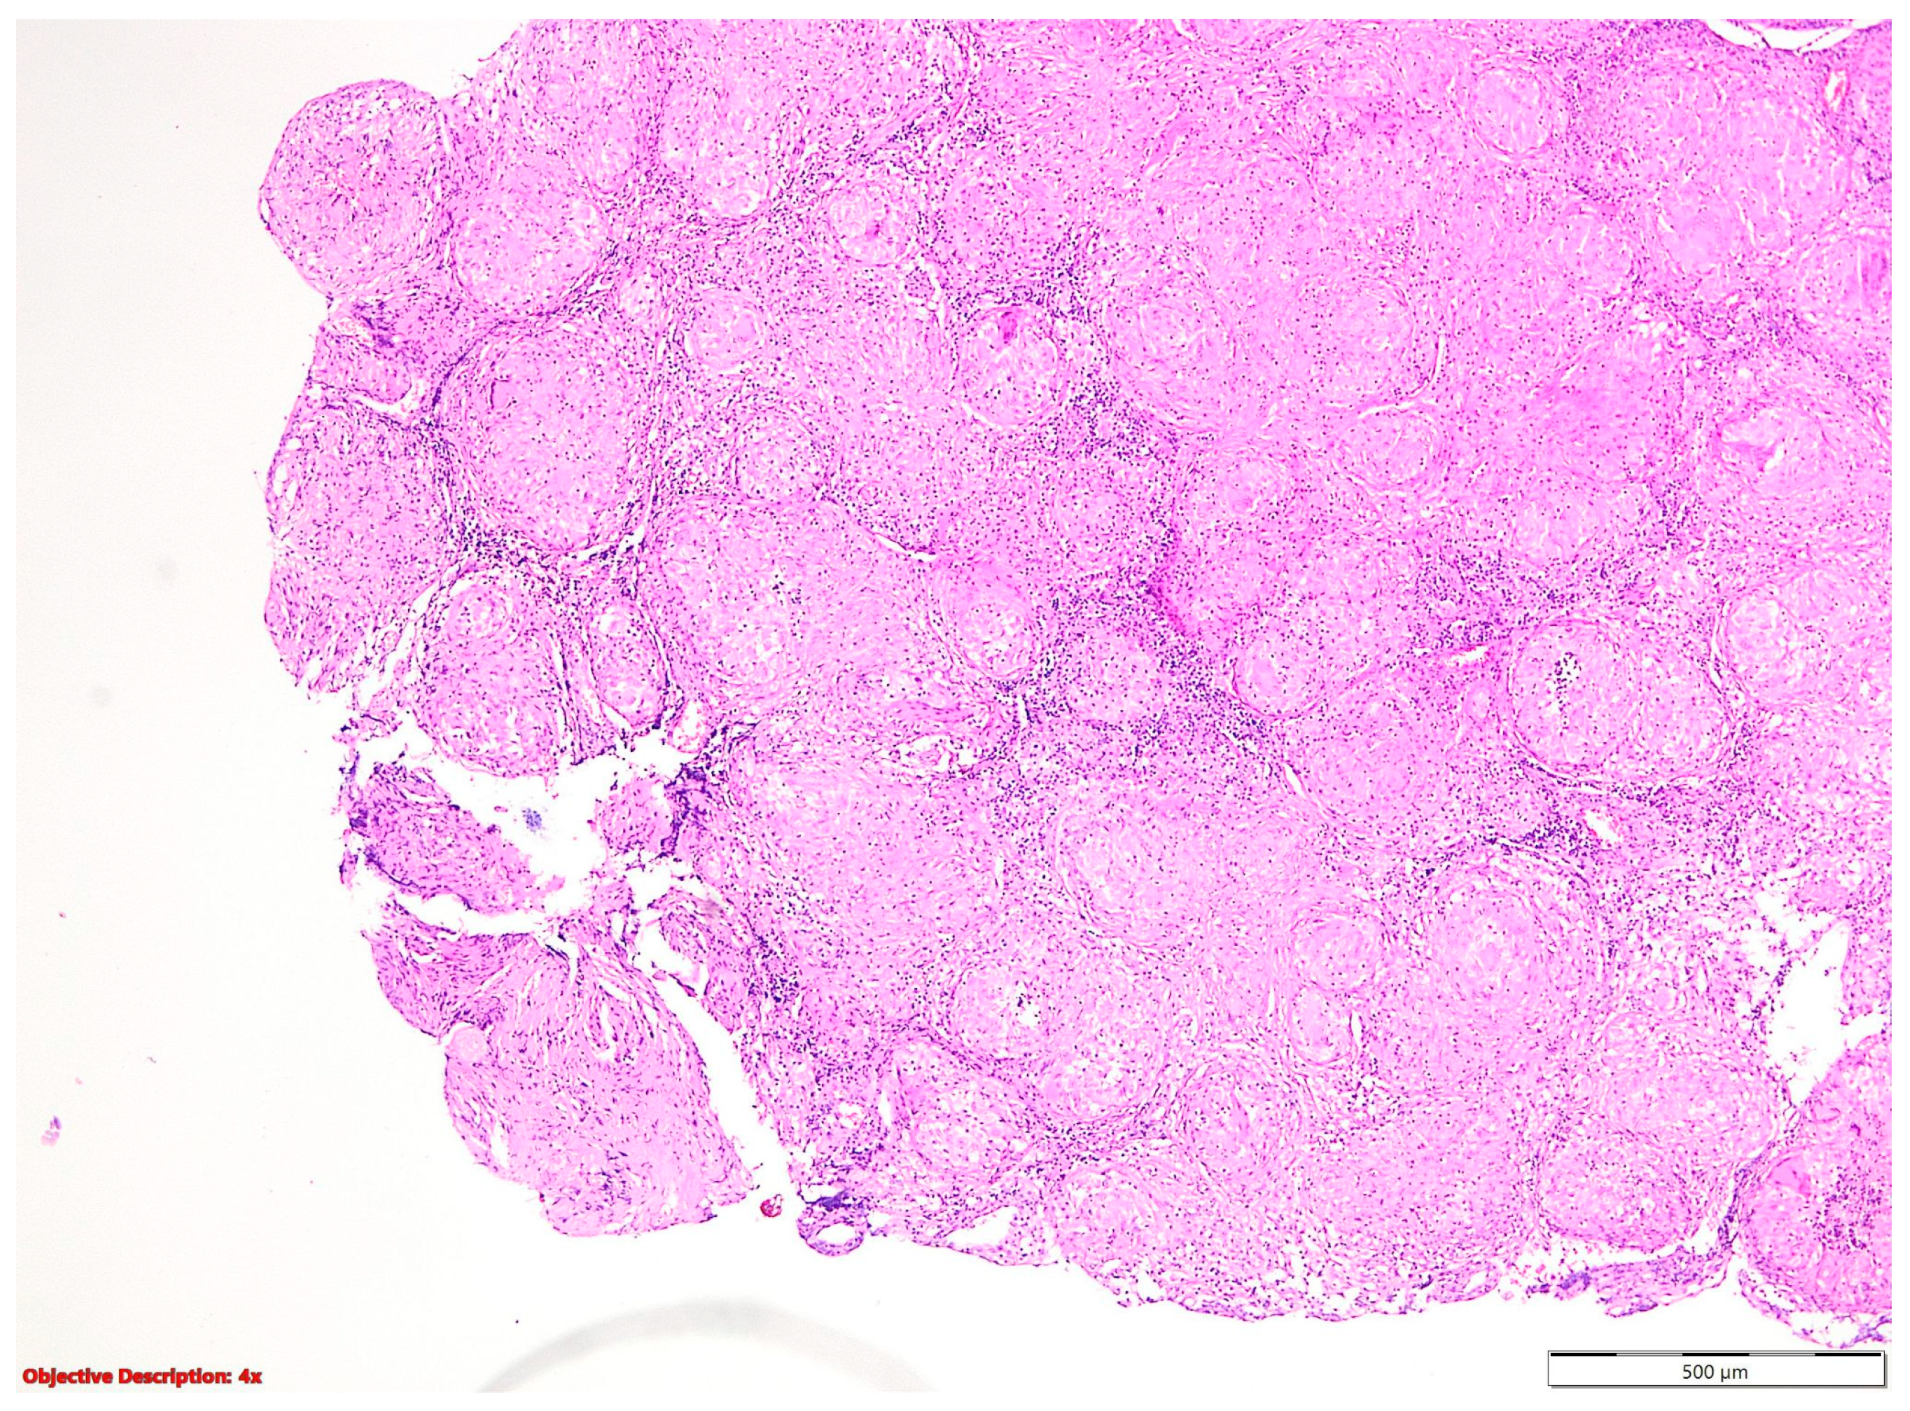

Figure 3. Sarcoidosis—well-formed noncaseating epithelioid granulomas; HE, 40×.

In the nine cases of NSCLC associated with granulomatous lesions, five of them were represented by active tuberculosis (Figure 2) and four by sarcoidosis (Figure 3).

Noncaseating granulomatous inflammation, with its potential to manifest as sarcoidosis, can impact multiple organs, contributing to a spectrum of clinical presentations [14]. Interestingly, sarcoidosis not only predisposes individuals to lung cancer but also shares clinical resemblances with viral, neoplastic, and other granulomatous conditions [15]. Although sarcoidosis and primary lung cancer infrequently coexist, their co-occurrence presents diagnostic challenges due to overlapping clinical features and histopathological findings [14]. This intricate relationship underscores the importance of a thorough clinical evaluation and histopathological examination to differentiate between these entities and guide appropriate management strategies.

Sarcoidosis is characterized by the presence of well-defined, compact, non-necrotizing granulomas primarily localized within the interstitium and excluding airspaces [16]. These granulomas are frequently observed in anatomical structures such as the pleura, interlobular septa, and broncho-vascular bundles, typically following lymphatic routes [16]. While a thin rim of chronic inflammation may surround these granulomas, it generally does not extend into the adjacent interstitium [16]. Although granulomas may occasionally contain small areas of central necrosis, such occurrences are typically inconspicuous [16]. Furthermore, these granulomas may harbor common multinucleated giant cells exhibiting various inclusions, including Schaumann or asteroid bodies (Figure 11) [16].